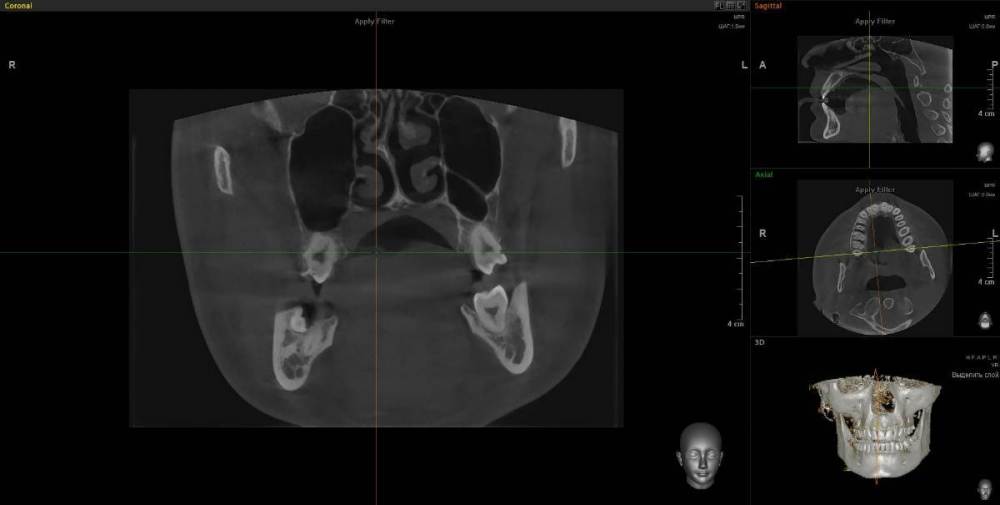

wladdX Опубликовано 17 января, 2024 Поделиться Опубликовано 17 января, 2024 (изменено) Думаю, что удаление зуба 46 - правильный выбор. Также имеется ретинированный зуб мудрости (48). С ним тоже лучше расстаться. У зуба 46 довольно широкая межкорневая перегородка, что даёт неплохие шансы на одномоментную установку имплантата. Зубы 18 и 28 (верхние зубы мудрости) наклонены щёчно, имеются кариозные полости недоступные для лечения - также на удаление Изменено 17 января, 2024 пользователем wladdX 2 Ссылка на комментарий

wladdX Опубликовано 17 января, 2024 Поделиться Опубликовано 17 января, 2024 Пора протезировать слева внизу 1 1 Ссылка на комментарий